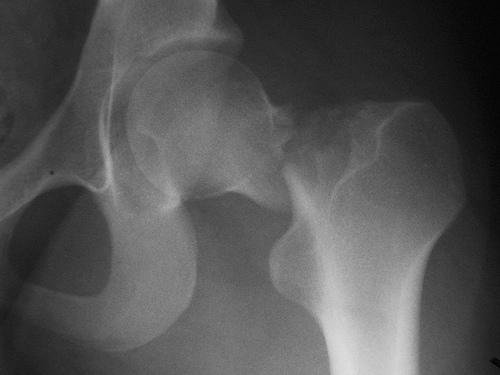

No se está tratando bien la osteoporosis luego de la fractura de cadera

23 julio 2018

Un estudio encuentra que menos del 10% de los pacientes había iniciado tratamiento para osteoporosis luego de 6 meses de la fractura, a pesar de los beneficios demostrados de los fármacos en esta indicación. JAMA Network Open, 20 de julio de 2018